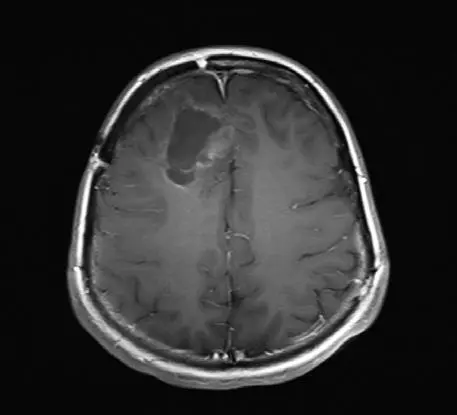

Сейчас проходят и вовсе поразительные клинические испытания. Ученые из Университета Дьюка используют другую иммунную стратегию, модифицируя вирус полиомиелита. Идее борьбы с раком с помощью вирусов больше ста лет, но необходимые для экспериментов технологии и технические новинки появились сравнительно недавно. Последний случай заражения полиомиелитом случился в США в 1979 году. Ученые Университета Дьюка заметили одно интересное свойство вируса: он убивает клетки, попадая в них через «дверь»-рецептор. Как оказалось, рецептор для вируса полиомиелита присутствует на большинстве клеток твердых опухолей – раков легких, груди, мозга, простаты, – а вот на большинстве нормальных клеток отсутствует. Проблема лишь в том, что вирус может прикрепляться еще и к клеткам нервной системы – нейронам. Когда вирус убивает их, это приводит к мышечному параличу. Если удалить болезнетворную часть вируса, заражающую нормальные нейроны, и подменить ее безвредным вирусом простуды, а ту часть, что прикрепляется к раковым клеткам и уничтожает их, оставить, то мы получим безопасный вирус. Вирус впрыскивается прямо в опухоль, заражает несколько раковых клеток и убивает их, в то же время активизируя иммунную систему. Она просыпается: «Эй, это же полиомиелит!» – и вместе с вирусом убивает еще и «ни в чем не повинные» клетки опухоли. Вирус, по сути, помечает опухоль как «чужеродный предмет» и заставляет иммунную систему тела идти в бой.

Исследования с вирусом полиомиелита на данный момент ведутся в основном на пациентах с продвинутой стадией глиобластомы – одного из самых смертоносных и агрессивных видов рака мозга, который часто убивает через несколько недель после того, как все стандартные способы лечения перестают работать. Ученым удалось продлить жизнь нескольких пациентов на месяцы и даже годы [9].

Энцефалограммы 20-летнего студента, которого лечат модифицированным вирусом полиомиелита (PVS-RIPO), вводимым через катетер, подсоединенный прямо к опухоли.